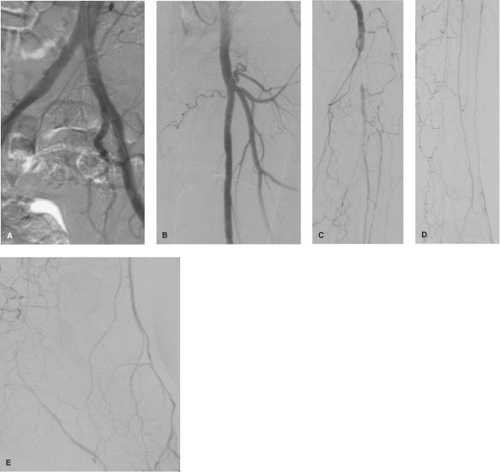

pta在医学上什么意思足背动脉旁路术:从技术革新到精准医疗_https://www.jmylbn.com_新闻资讯_第12张

动脉内数字减影血管造影显示糖尿病性闭塞病变的特征性分布模式:主动脉、髂动脉(A)、股浅动脉及腘动脉(B)未受累;胫/腓动脉(C、D)呈弥漫性病变,而足背动脉(E)保持通畅。